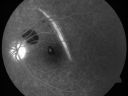

Multifocal Choroiditis and Subretinal Fibrosis - 32 yo Female Montage Initial Visit806 views32-year-old woman vision loss in the right eye associated with macular scarring and multifocal choroiditis in 1999 with new vision loss in left eye: OD 20/400, OS 20/50.

2 months post-rx with posterior subtenons kenalog and intravitreal avastin - va os 20/30 and lesion has retracted and organized. It never subsequently grew over 2 years follow-up